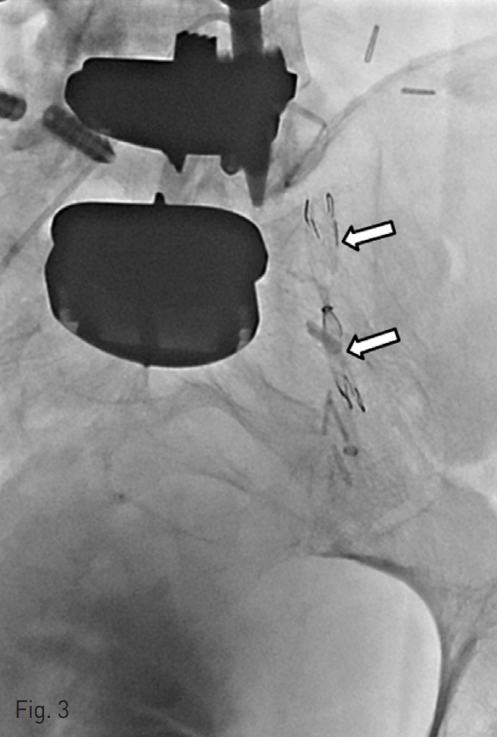

Prior to embolization of the fistulous tract, we decided to place a ureteral occlusion stent in the remnant left ureter in order to prevent the spillage of embolic material into the bladder (Fig. 3). The ureteral occlusion stent (S&G Biotech; Seongnam, Gyunggi-do, Korea) was internally coated with a thin silicone membrane with the central portion completely obstructed in a candy-wrapper configuration.

Fig. 3

The ureteral occlusion stent (arrows) was deployed in the left remnant ureter in order to prevent the spillage of embolic material into the bladder prior to embolization.